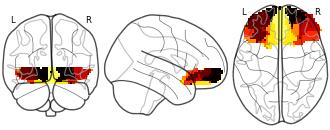

Connectivity-Based Parcellation of the Human Orbitofrontal Cortex: K=7...

License information was derived automaticallyDescriptionK=7 cluster map based on N=13 participants.

K-means cluster maps of orbitofrontal cortex with K=2, 3, 4, 5, 6, and 7 clusters based on resting-state fMRI data.